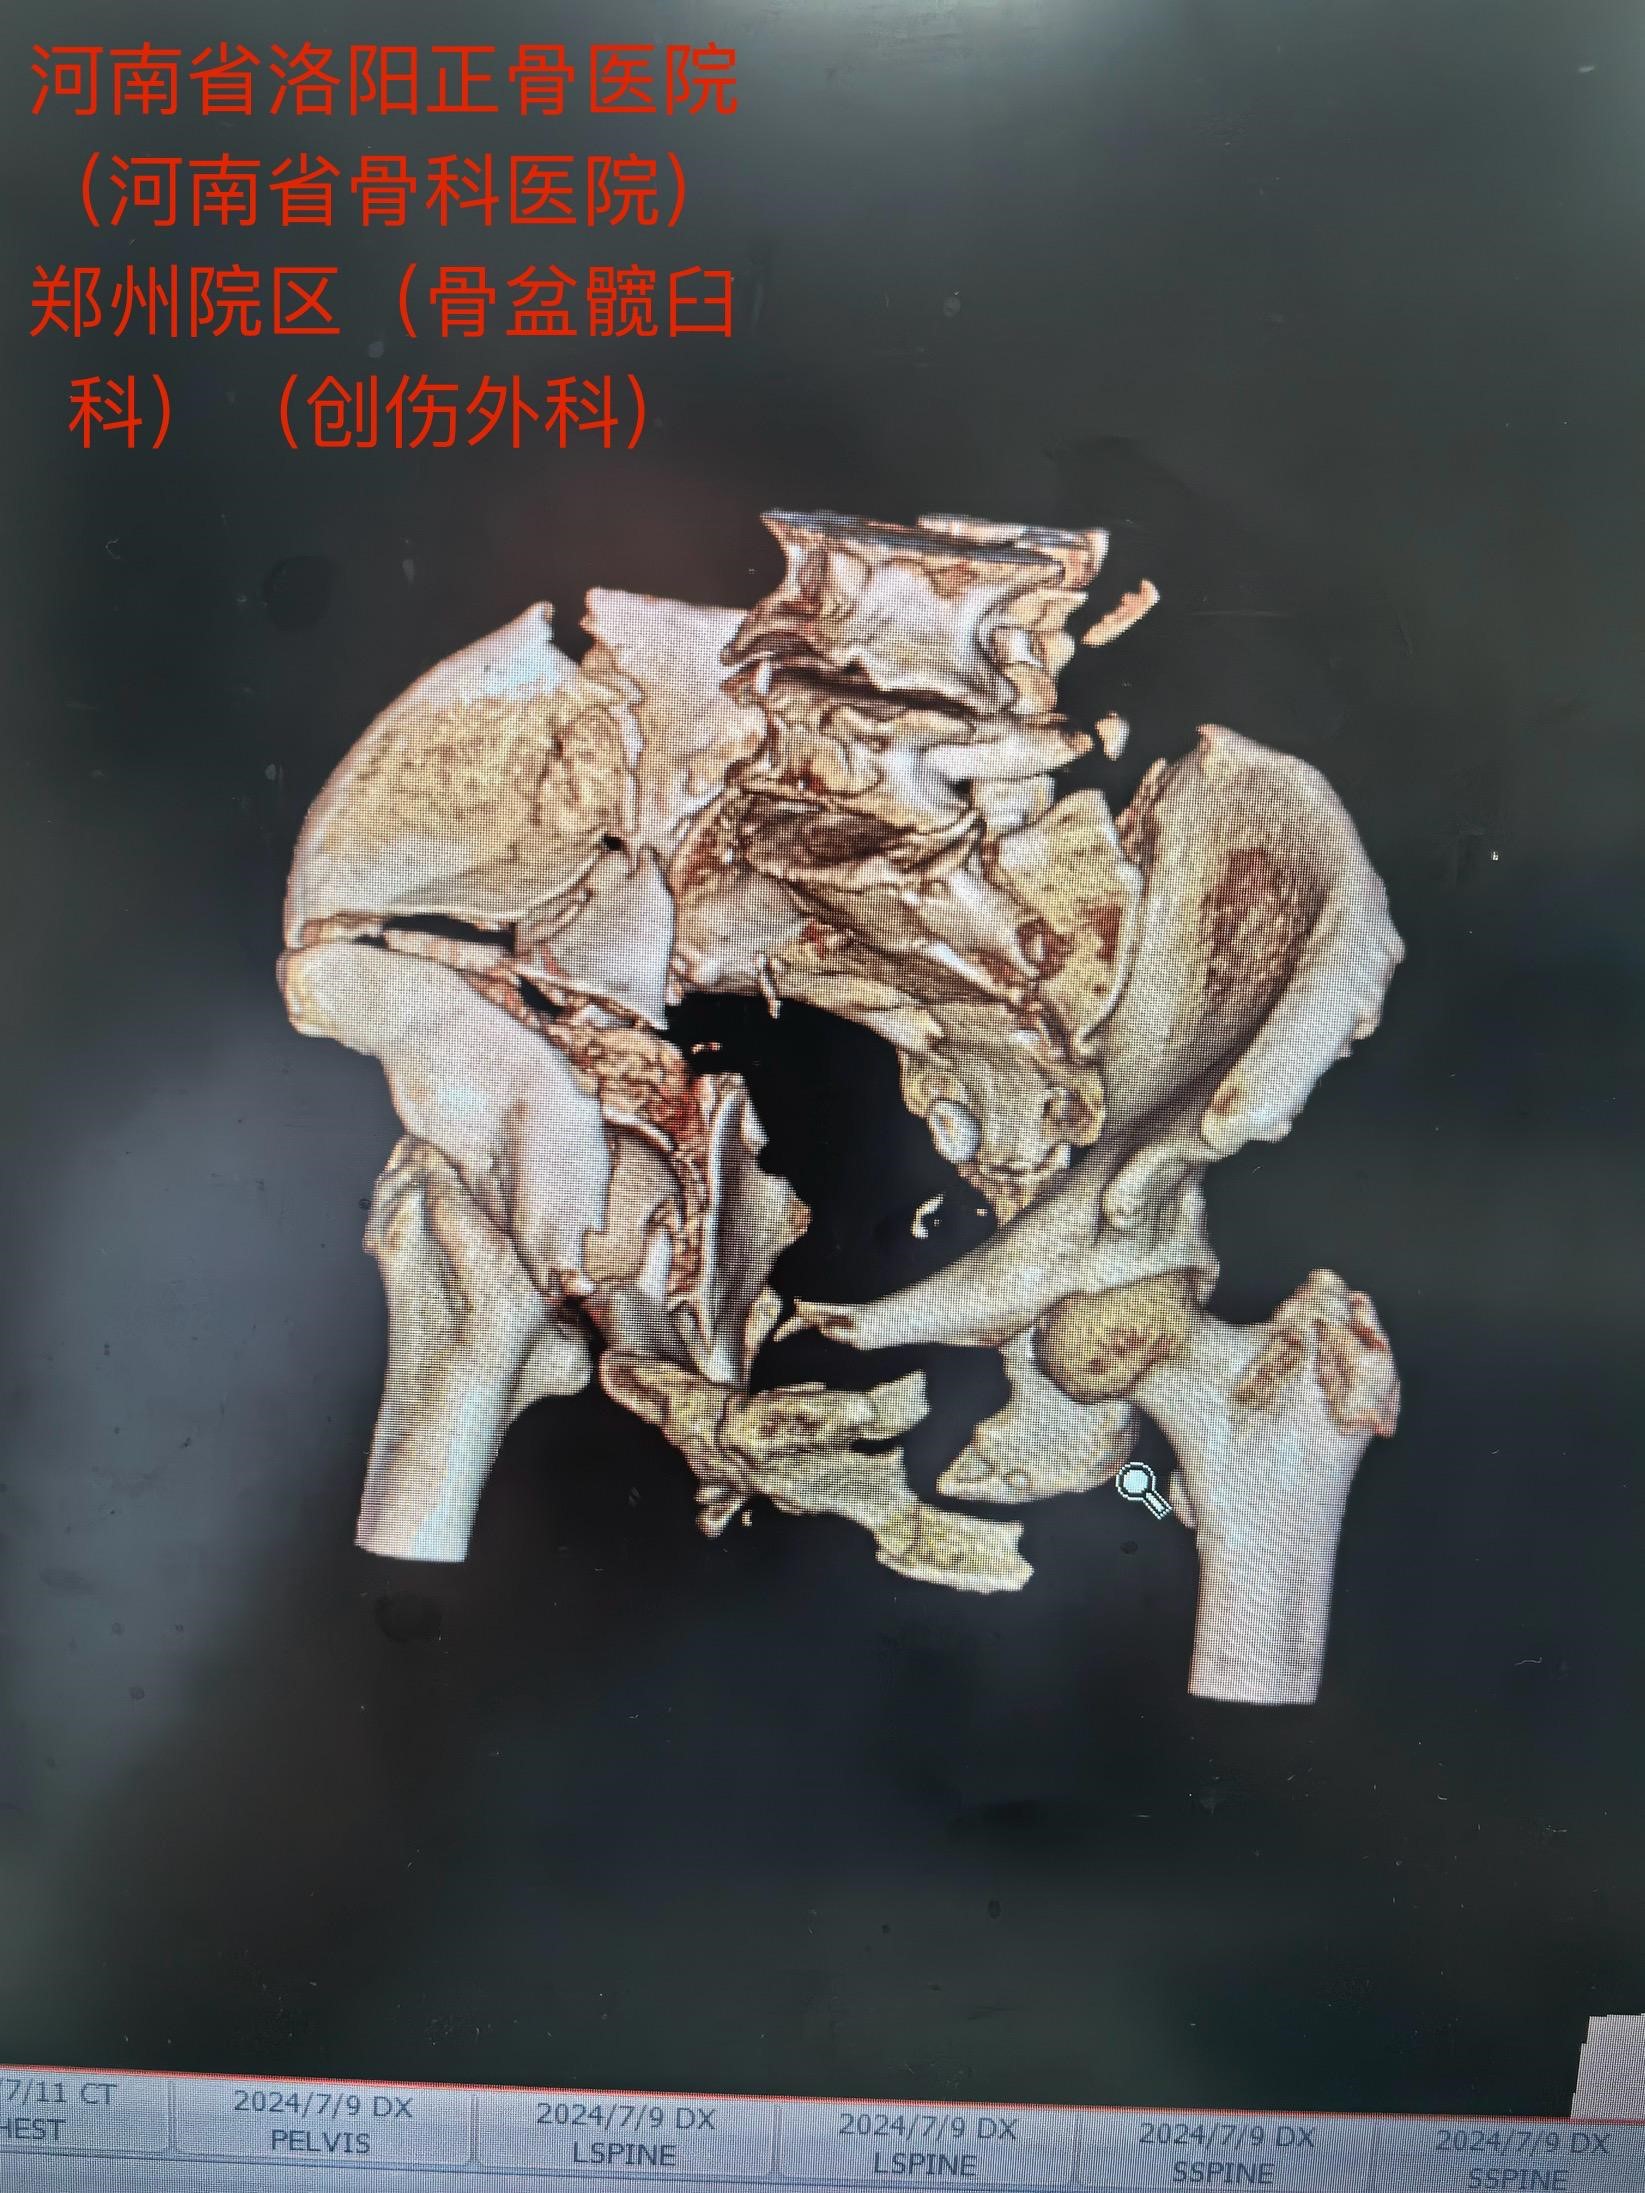

老人今年73岁,遭遇车祸后全身多处伤,在当地医院ICU治疗,生命体征平稳后,转入我院郑州院区。影像检查诊断:骨盆合并髋臼骨折,右侧髋臼双柱骨折……

马献忠主任积极倡导加速康复外科理念,对于老年骨盆髋臼骨折患者,他主张积极治疗。面对老人的复杂病情,马献忠主任积极组织多学科会诊,充分讨论,详细制定术前规划,为老人量身定制治疗方案。马献忠主任分两期进行手术:1期,右侧骨盆髋臼行单一髂腹股沟入路进行骨折复位及前后柱的固定。2期,进行左侧的微创骶髂螺钉固定骨盆后环。